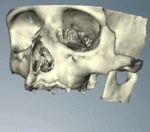

CT scans can be loaded to CAD/CAM software to create a simulation of the desired treatment. Virtual implants are then placed and a stent created on a 3D printer from the data.

When a more exacting plan is needed beyond clinical judgment, the dentist will make an acrylic guide (called a stent) prior to surgery which guides optimal positioning of the implant. Increasingly, dentists opt to get a CT scan of the jaws and any existing dentures, then plan the surgery on CAD/CAM software. The stent can then be made using stereolithography following computerized planning of a case from the CT scan. The use of CT scanning in complex cases also helps the surgeon identify and avoid vital structures such as the inferior alveolar nerve and the sinus.[17][18](p1199)